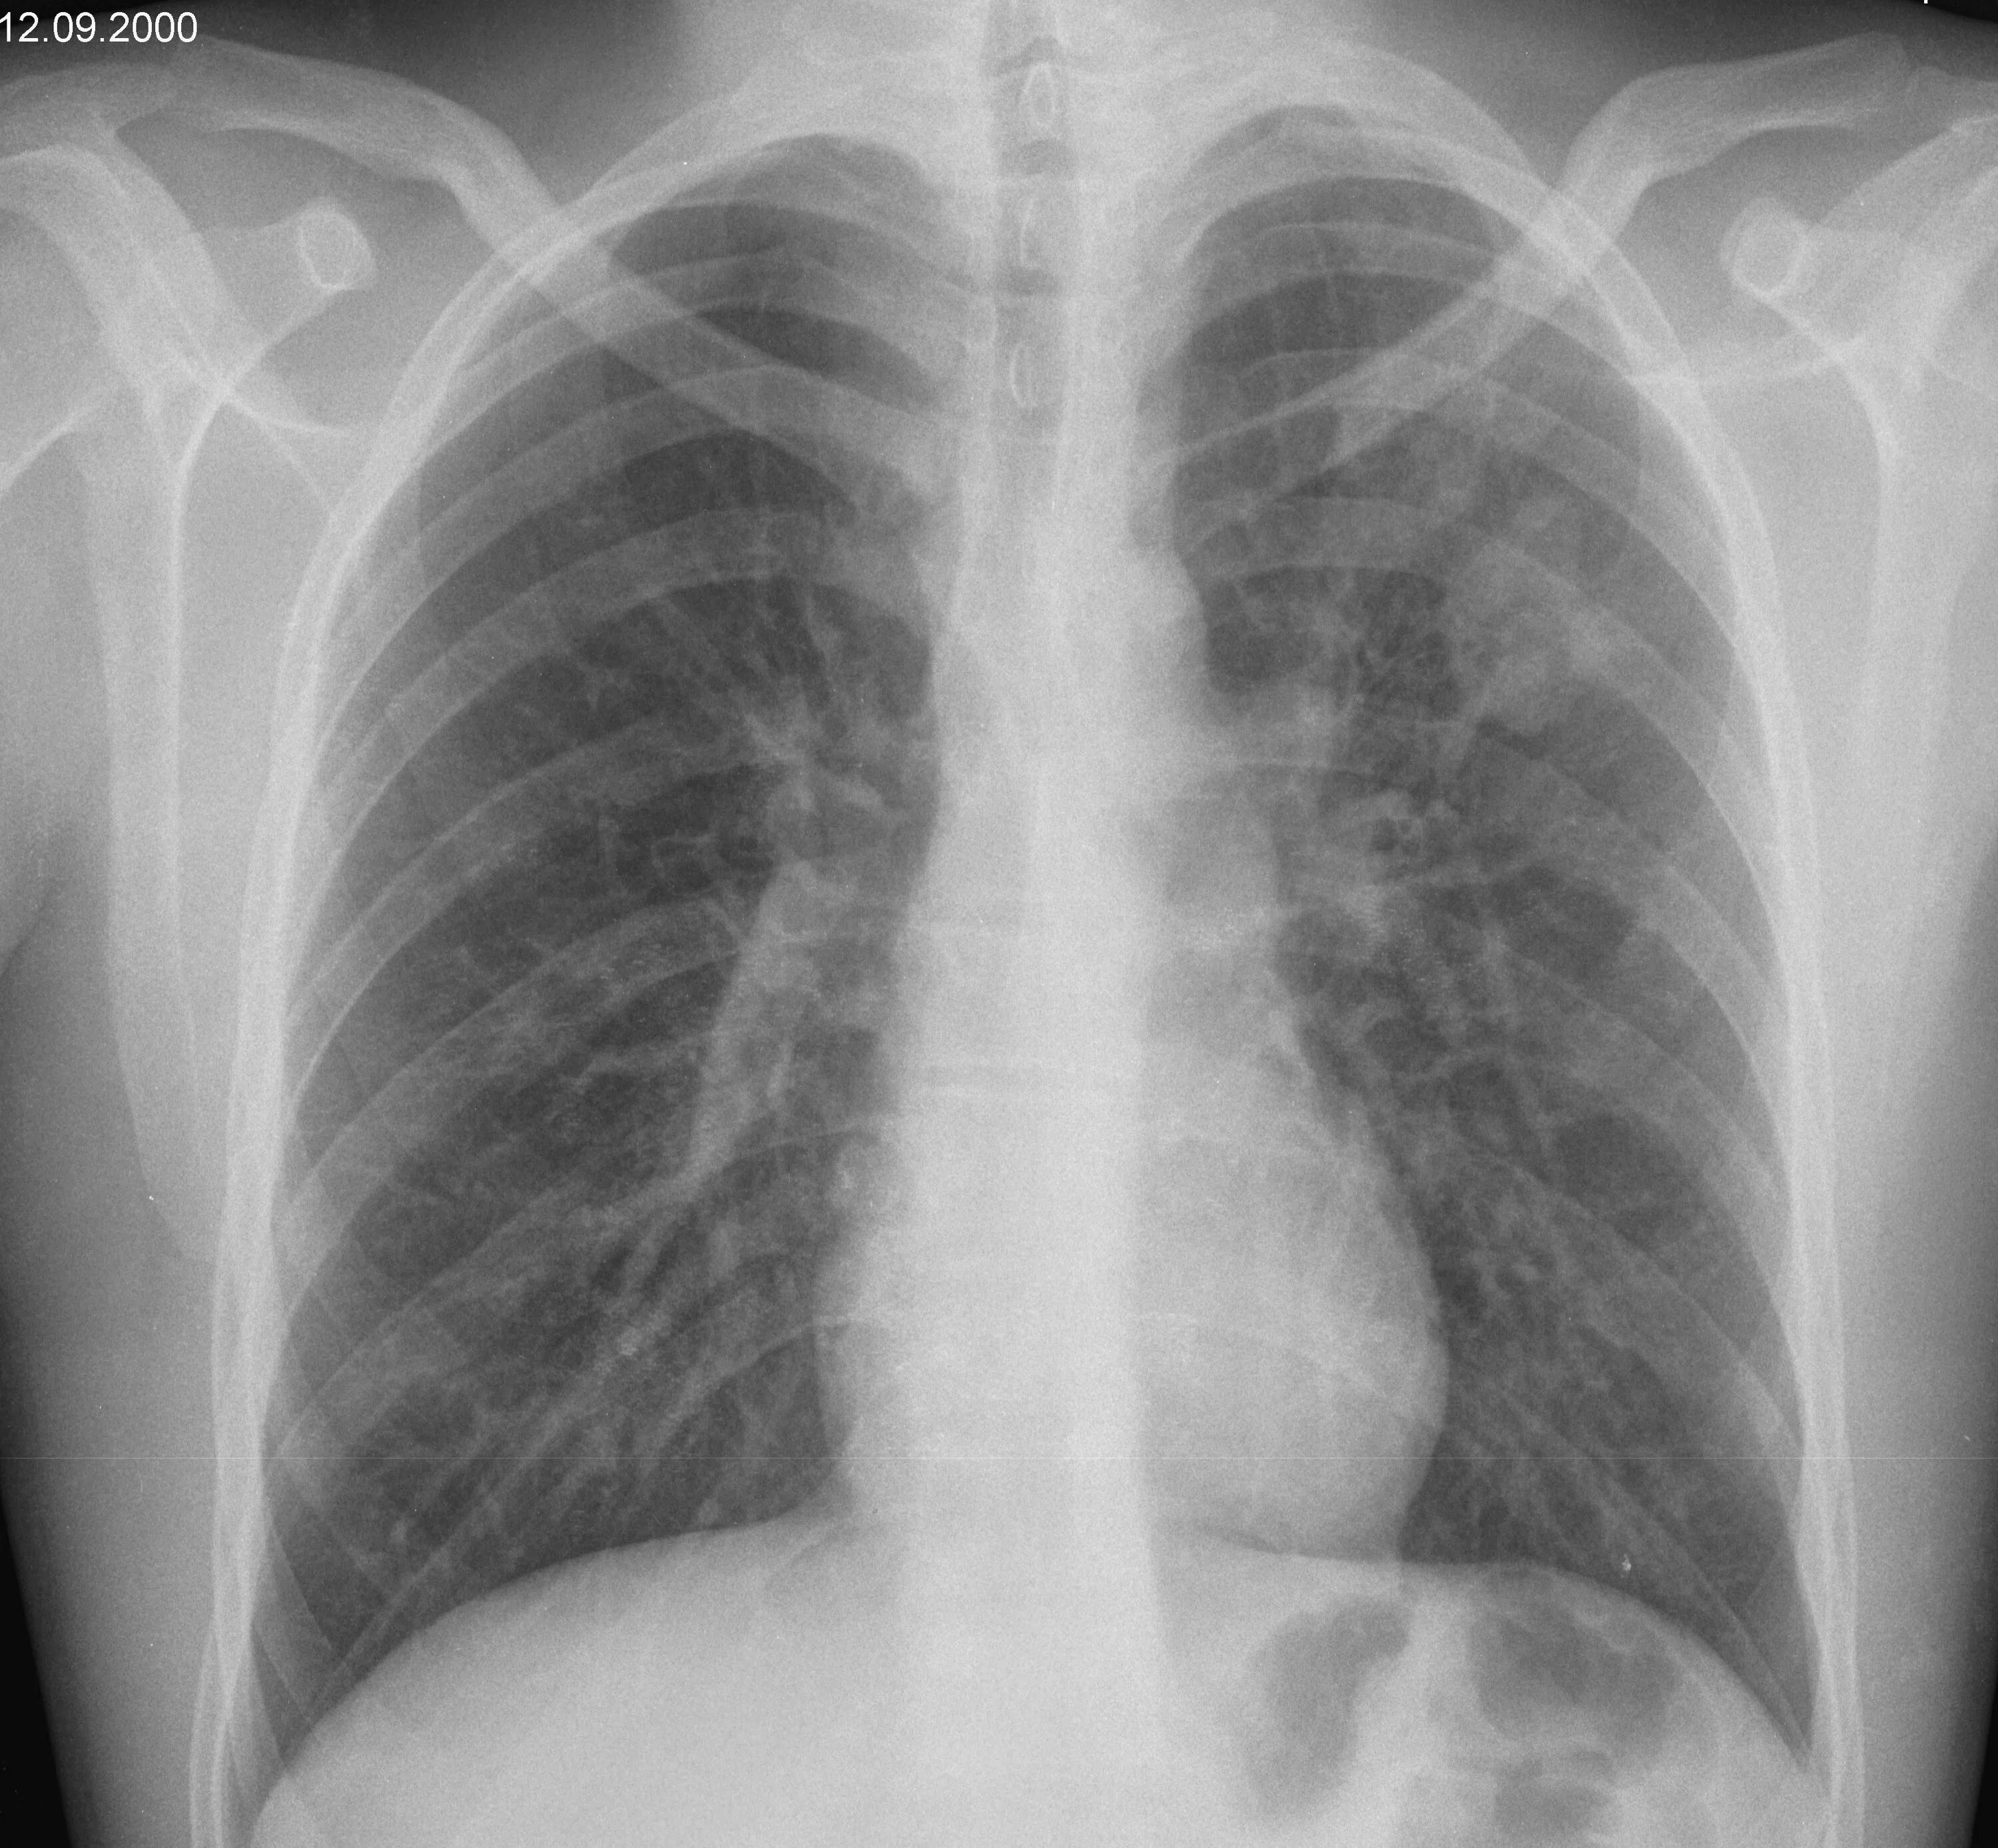

Образование в легком форум